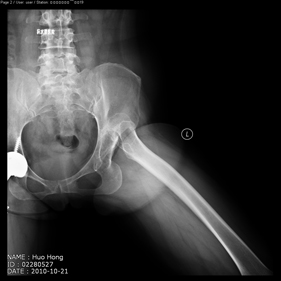

- total hip replacement on hips with u…

- rivision total hip replacement for d…

shortening osteotomy and total hip replacement for bilateral severe dysplasia of hip with high riding